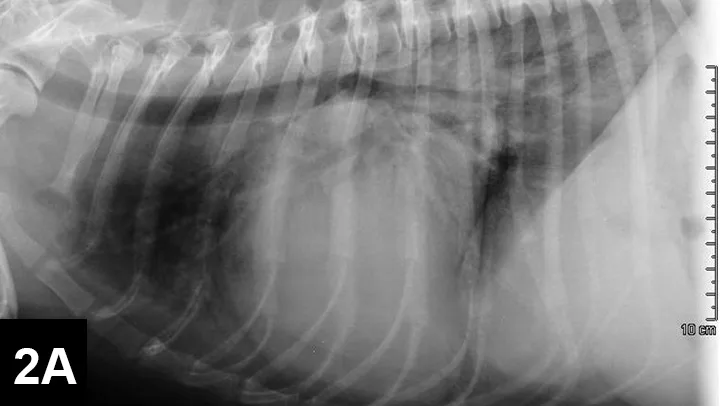

Featured Image

FIGURE 2B

VD thoracic radiograph

A murmur and regular rhythm were auscultated. The heart rate was approximately 180 bpm, and crackles were auscultated in the caudodorsal lung fields. A 6 lead electrocardiogram (ECG, Figure 1) and thoracic radiographs (Figure 2A and 2B) were performed.

A sinus rhythm (HR is ~150 bpm) and left ventricular enlargement pattern were noted on ECG: the sensitivity was decreased to 5 mm/mV, and R waves measured ~3 mV (upper end of normal R-wave height is 2.5 mV). Thoracic radiographs revealed severe left atrial enlargement with moderate left ventricular enlargement. There was a moderate interstitial to alveolar pulmonary pattern most pronounced in the caudodorsal lung fields, which is consistent with left-sided congestive heart failure resulting from degenerative mitral valve disease.